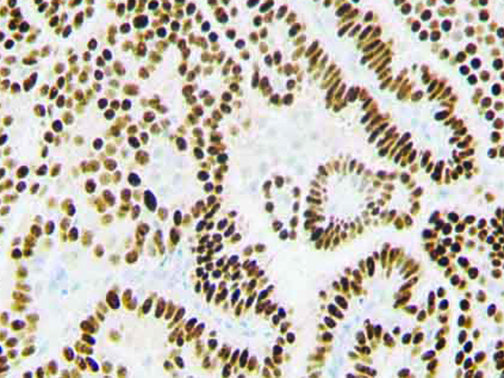

The first cytokines released are interleukin 1β (IL-1β) and tumor necrosis factor-α (TNF-α), which attract a variety of circulating white blood cells (WBCs) to the infection site, including neutrophils, monocytes, macrophages, and natural killer (NK) cells. This response, along with the antipathogenic chemicals released by these cells (i.e., complement), comprise the innate immune response. These cells directly attack the invading pathogen and also release additional cytokines, chief among them interleukin-1 and 6 (IL-6). IL-6 is essential for invoking the adaptive immune response, which calls T-cells, B-cells, and T helper (Th) cells to the infection site. IL-6 also stimulates further recruitment, proliferation and activation of macrophages.

It is the ICU physician who is most likely to witness one of the deadliest manifestations of the abnormal immunological response, the cytokine storm syndrome (CSS). This response is also referred to by some as the cytokine release syndrome (CRS). CSS is characterized by continuous activation and expansion of macrophage and lymphocyte populations, which secrete large amounts of cytokines, causing the cytokine storm. This massive cytokine release is akin to hemophagocytic lymphohistiocytosis (HLH) disease, a syndrome characterized by initial unchecked and persistent activation of cytotoxic T lymphocytes and NK cells.